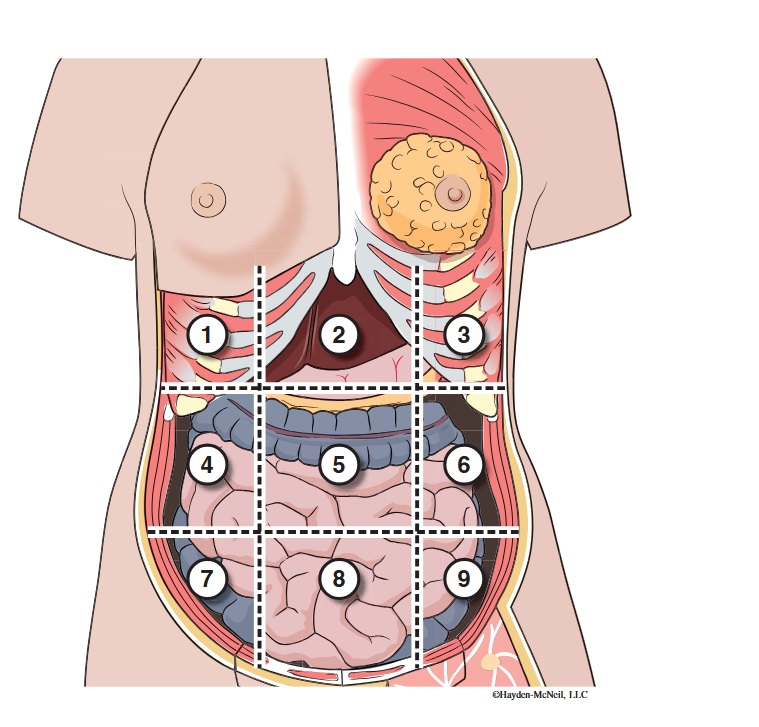

What abdominal region is labeled #1?

right hypochondriac

What abdominal region is labeled #2?

epigastric

What abdominal region is labeled #3?

left hypochondriac

What abdominal region is labeled #4?

right lumbar

What abdominal region is labeled #5?

umbilical

What abdominal region is labeled #6?

left lumbar

What abdominal region is labeled #7?

right iliac/ inguinal

What abdominal region is labeled #8?

hypogastric

What abdominal region is labeled #9?

left illiac/ inguinal

What organs are apart of the right hypochrondriac region?

right lobe of liver, gallbladder, right adrenal gland

What organs are apart of the epigastric region?

pyloric end of stomach, duodenum, pancreas

What organs are apart of the left hypochondriac region?

stomach, spleen, left adrenal gland

What organs are apart of the right lumbar region?

ascending colon, right kidney, portion of small intestine

What organs are apart of the umbilical region?

omentum, mesentery, small intestine

What organs are apart of the left lumbar region?

descending colon, left kidney, portion of the small intestine

What organs are apart of the right iliac/ inguinal region?

cecum of large intestines, appendix, right ovary

What organs are apart of the hypogastric region?

ileum, bladder, uterus

What organs are apart of the left iliac/ inguinal region?

sigmoid colon, left ureter, left ovary